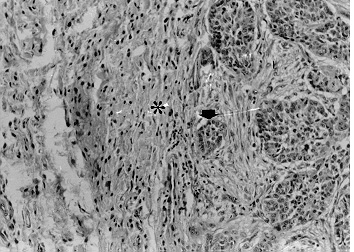

Microfotografia de corte histopatológico mostrando invasão tumoral (seta) da membrana tireohióidea (*H.E. X 132)